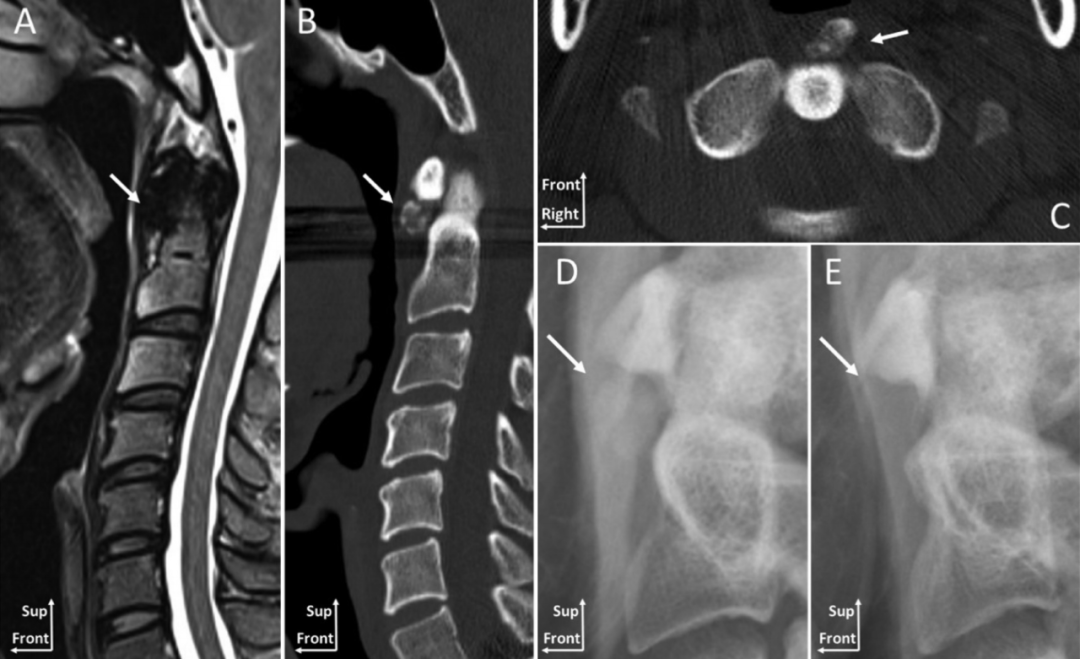

一位88岁女性患者,主诉急性颈痛伴发热2个月入院。体温波动在38-39.3℃,无视力模糊,无神经及脊髓压迫征象。颈椎CT+矢状位重建显示寰椎横韧带的曲线状钙化(图A,箭头所示),线性钙化(图B,箭头所示),以及齿状突周围的冠状钙沉积(图C,箭头所示)。给予短期非甾体抗炎药和泼尼松龙(15mg/d)后,其上述症状完全缓解。同时,作者指出这类疾病通常不需要长期用药。